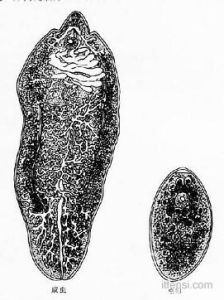

肝吸蟲病吸蟲學名稱為,中華分枝睪吸蟲成蟲寄生在人或動物的膽管內成蟲壽命可達20-30年或更長時間,蟲體攝取宿主的紅細胞白細胞,並不斷排出代謝產物和分泌有毒物質損害,宿主成蟲不斷排出蟲卵蟲卵隨膽汁進入消化道與糞便一起排出體外,肝吸蟲卵是人體腸道寄生蟲中最小的蟲卵之一蟲卵,形態略似電燈泡蟲卵在適宜的外界環境中不斷發育孵出幼蟲,幼蟲遇到淡水螺類並被吞食後則在螺體內發育成第二期幼蟲即尾蚴,此時尾蚴從螺體內逸出不斷地在水面上遊動,如果遇到淡水魚蝦尾蚴則即附著魚體並侵入魚蝦組織形成具有感染性的,幼蟲即囊蚴這時如果吃了含有肝吸蟲囊蚴的,小魚小蝦或生魚片沒有煮熟的魚蝦以及被肝吸蟲囊蚴污染的,其它食物等均可引起感染發病。